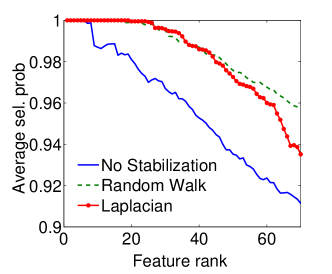

|

|

| (a) Cumulative, | (b) Stagewise (Shared), |

|

|

| (c) Stagewise (Separate), | (d) Stagewise (Separate), |

We now examine the models stability against data sampling and evaluate the stabilizing property of the proposed method (Sec. 6.2). For each fold, we generated samples, each of which was drawn randomly from % of training data. Each example resulted in a model, and the feature weights were recorded and finally the results of all folds – models – were combined. Figs. 5(a–d) show the indices (Eq. (5)) as functions of the rank list size , for all ordinal classifiers. The instability is clearly an issue – the average selected probability drops as more features are included. Using both the Laplacian and random walk regularization methods (Eqs. (9,10)), the improvement in stability is evidenced in all settings. The instability and stabilizing effect were similarly obtained with the indices (Figs. 6(a–d)).